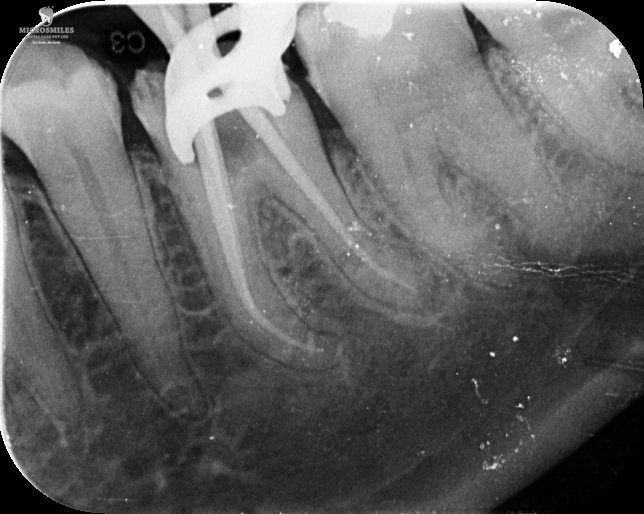

Our treatments are performed using advanced dental microscopes that magnify up to 25x- allowing us to identify previously hidden canals, fractures, or infected areas that standard tools may miss. This level of detail means faster, more accurate procedures and fewer surprises, giving your tooth the attention it truly deserves.